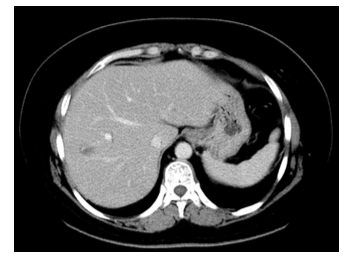

2.胸部CT平扫(图1):两肺小结节,部分淡薄;左肺舌段纤维灶;左乳占位伴皮肤增厚。双侧腋下淋巴结显示,右侧腋下一肿大淋巴结。左乳可见数个结节影,较大者位于左乳头后方,大小约21.7 mm × 17.4 mm,伴左乳晕周围皮肤增厚。双侧腋下淋巴结显示,右侧腋下一肿大淋巴结,短径约13.6 mm。

图1 2018年5月 胸部CT平扫(基线)